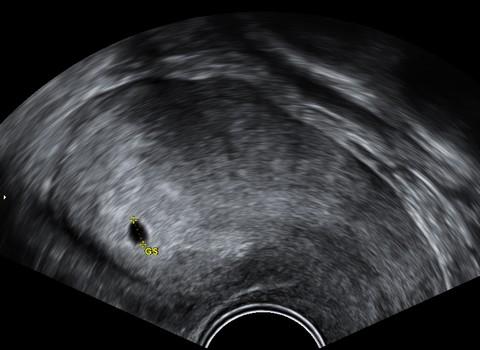

Na ultrazvukovém snímku je vidět gestační váček na konci 4. týdne (4+0) o velikosti 4,7 mm.